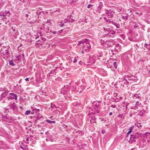

Gastric bleeding is the result of calcification of elastic fibers in the thin-walled arteries located immediately beneath the gastric mucosa. The internal elastic lamina is particularly affected. In muscular arteries, such as the coronary arteries and the large peripheral arteries, calcification begins in the intemal and external elastic laminae, leading to their fragmentation, and subsequently extends to the media and intima . Calcification of the elastic fibers in the endocardium is a common occurrence but is clinically silent . |

Histogenesis. Electron microscopic examination shows that the calcification occurs in normal-appearing elastic fibers . In some patients, especially in young persons, only some of the elastic fibers in the lower dermis are calcified, and the calcification is variable in degree. However, in adult patients, most elastic fibers show considerable calcification and, as a result, degeneration. Early calcification of elastic fibers consists either of diffuse granular deposits throughout the elastic fiber or of dense aggregates that may be located in the center or near the margin of the fiber (EM 5). With progression of the calcification, the elastic fibers ultimately become fully calcified, showing marked swelling and bizarre distortions. In addition, heavy calcium deposits may be seen in the ground substance adjacent to elastic fibers and free in the ground substance. The presence of calcified material outside of elastic fibers can be explained by the disintegration of completely calcified elastic fibers . |